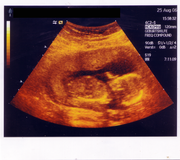

Ultrazvuk

Sonografie

Ultrazvuk se dá použít třeba při lékařském vyšetření. Ultrazvukové vlny procházejí tělem a odrážejí se od jednotlivých orgánů resp. od přechodů mezi tkáněmi s různou akustickou impedancí.